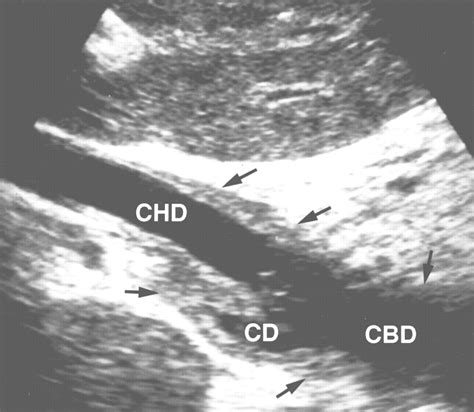

The common bile duct is a tube-like structure formed by the union of the common hepatic duct and the cystic duct. Its primary function is to deliver bile, which is produced by the liver and stored in the gallbladder, into the duodenum. The dimensions of this duct are clinical indicators of health; when the normal common bile duct size is exceeded, it is often a diagnostic clue for radiologists and gastroenterologists that bile flow is being restricted, perhaps by a gallstone, a tumor, or stricture.

1. Abdominal Ultrasound: A non-invasive test that uses sound waves to create images of the gallbladder and bile ducts. It is the gold standard for initial screening.